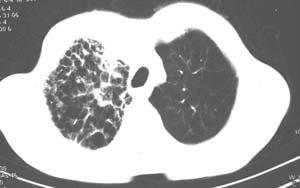

右肺上叶见片状 网格状及索条致密影.其内参杂斑点状小结节,部分融合,密度不均匀,内见含气支气管像,纵隔内见肿大淋巴结,其他肺呈代偿性肺气肿像.结合男 64  咳血,咳痰 发热 3天 血象1.2万,综合考虑:1 慢性炎症伴间质纤维化 肺气肿.2 不除外特发性感染的可能.

右肺上叶大片片状、网格状及索条致密影,前半部密实向后逐渐疏松,其内参杂斑点状小结节,密度不均匀,内见含气支气管像,纵隔内见肿大淋巴结,其他肺呈弥漫性小叶中心性性肺气肿改变,结合男 64  咳血,咳痰,发热3天,血象1.2万。考虑:1 慢性支气管炎、肺气肿合并右上肺感染。2 不除外结核合并感染的可能。

右肺上叶见片状 网格状及索条致密影.其内参杂斑点状小结节,部分融合,密度不均匀,内见含气支气管像,前段有一小片结影,纵隔内见肿大淋巴结,右侧胸腔少量积液。.结合男 64  咳血,咳痰 发热 3天 血象1.2万,综合考虑:2 右上肺感染伴间质纤维化 2 警惕细支气管肺泡癌。3建议结合临床及进一步检查[痰及纤支镜]或治疗后复查

右侧胸廓略小于左侧,右肺上叶大片实变影,近肺门处密度较高,内见支气管气相,周围较淡,呈网格状,余肺野清晰,纵隔内见肿大淋巴结,右侧胸腔少量积液。临床 咳血,咳痰 发热 , 血象1.2万。

考虑大叶性肺炎。

鉴别,细支气管肺泡癌,弥漫性可有病变侵犯一个肺叶,呈炎性实变,密度偏高,可见支气管气相、蜂窝状气腔,与本例影像上不易鉴别,但临床多为咳嗽、咳白色泡沫痰,感染症状轻。

影像表现:肺窗示右肺上中叶均可见小片、条索状、小结状密度增高影,可见支气管充气相,小叶间隔增厚,支气管通畅,余肺未见明显异常。纵隔窗示4r可见小淋巴结融合,无明显肿大,右侧示少量胸腔积液。

诊断:提示右肺上中叶感染性病变,tb可能大。

男 64  咳血,咳痰 发热 3天 血象1.2万;右肺上叶满布片絮状致密灶,其内见含气支气管影,右主支气管狭窄,纵隔内见肿大淋巴结。考虑右肺中央型肺癌伴阻塞性肺炎,建议支气管镜检查。

右侧胸阔塌陷,纵隔右移。右上肺大片状高密度影,沿支气管血管束走行,内见点状钙化;支气管充气征阳性,支气管呈柱状扩张;胸膜下小叶间隔增厚;右侧后胸壁内侧见带状水样密度影;纵隔淋巴结增大。

考虑:①右上叶陈旧性结核合并感染可能大。②右侧少量胸水。

影像学表现:右肺上叶大片状、网格状及索条致密影,前半部密实向后逐渐疏松,其内参杂斑点状小结节,密度不均匀,内见含气支气管像,纵隔内见肿大淋巴结.

综上,以右上肺tb(干酪性肺炎)首先考虑.当然大叶性肺炎不能除外.(血象不是特别高,纵隔内淋巴结肿大,也不甚支持.).如果经积极抗感染治疗,病灶明显好转.更能明确为大叶性肺炎.也不能明确排除肺ca.建议痰培养和纤支镜.